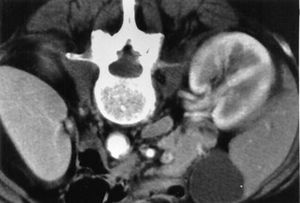

تلاحظ عداوى السبيل البولي المصحوبة بمضاعفات والتهاب الحويضة والكلية في المرضى كبار السن المصابين بشذوذات بنيوية أو انسداد مثل تضخم البروستات أو المثانات عصبية المنشأ أو في المرضى الذين يستخدمون قثاطر بولية. يظهر التهاب الحويضة والكلية اليمنى بال E coli في الصورة أسفل.

يمكن أن يجرى المسح المقطعي المحوسب أو تخطيط الصدى في عداوى السبيل البولي لمشاهدة أي مصدر آخر من الخراجات أو الحصى أو الانسداد.